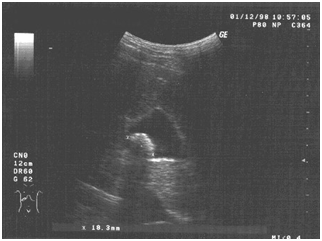

Data from the final ultrasound (at the end of the 6-week course of treatment) revealed an actual absence of echoes of inflammation of the gallbladder wall, mobility of the calculus and a reduction in its maximum size to 11.2mm (Figure 3). Ultrasound examination after a nutritional load indicated some hyperkineticity of the gallbladder wall (a reduction in the volume of the gall bladder 77% of the original). The course of treatment of the patient T. F-ko was interrupted in connection with her departure for a long period abroad. During the following years, experimental work was continued to investigate the possibility of conservative treatment of cholelithiasis complicated by chronic cholecystitis, involving volunteer patients. During this period, 7 people (3 men and 4 women) aged 35 to 54years old participated in the experiments, with different physique, severity and length of illness.

Figure 3 Final ultrasound examination of the gallbladder patient.